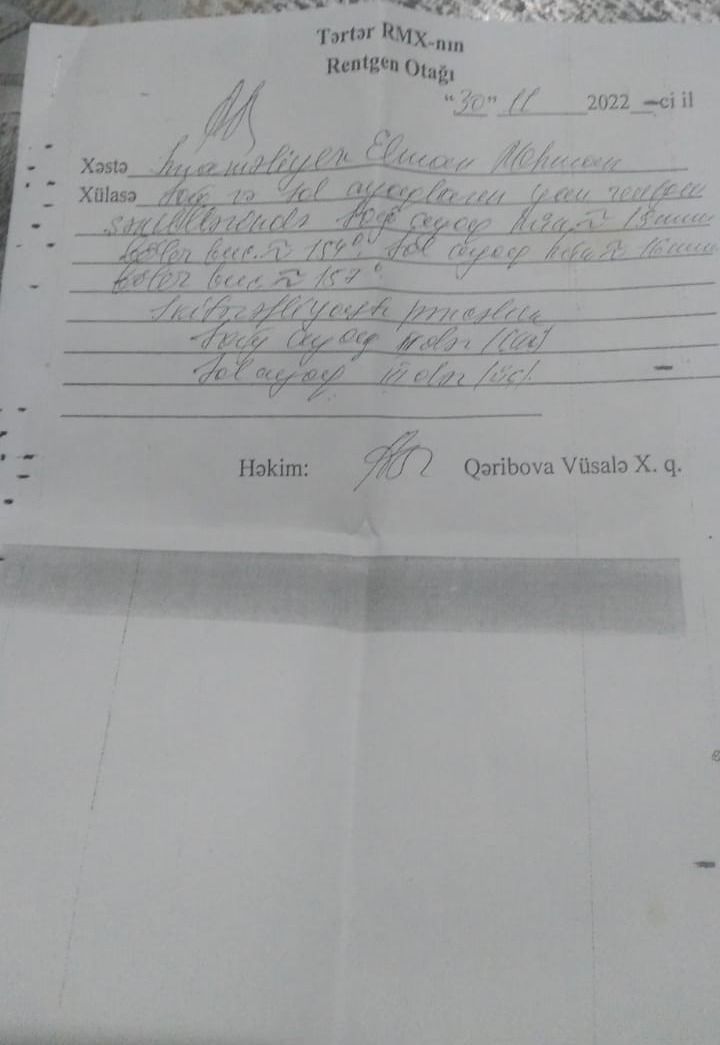

“Oğlum Elman İmaməliyevin ikitərəfli yastıpəncəlik səbəbilə hərbi xidmətə yarasızdır. Bu, Tərtər Rayon Mərkəzi Xəstəxanasından verilən rentgen kağızı ilə təsdiq olunub. Lakin hərbi xidmətə çağırış idarəsinin mayoru oğlumun hərbiyə xidmət üçün yararlı olduğunu əks etdirən saxta sənəd əldə edib. Hansı ki, oğlumun sol ayağı 3-cü, sağ ayağı isə 2-ci dərəcəli ikitərəfli yastıpəncədir.

Hərbi xidmətə çağırış idarəsinin komissiya həkimi rentgen kağızlarını da verib. Amma idarədəki mayor Şahverdiyev uşaqla prinsipə düşdüyü üçün saxta sənəd alıb. O, uşağı təhqir edib, uşaq da deyib ki, səni vuraram. İndi tələb edirəm ki, siz hansı sənədə əsasən müəyyən etmisiz ki, oğlumda hər iki ayağı üçüncü dərəcə yastıpəncədir? Həmin sənədi mənə vermirlər. Deyirlər ki, uşaq yararlıdır, aparırıq. Amma ona verilən möhlət kağızında isə 45-ci və 49-cu maddəyə əsasən, uşağın müalicə almalı olduğu yazılıb”.